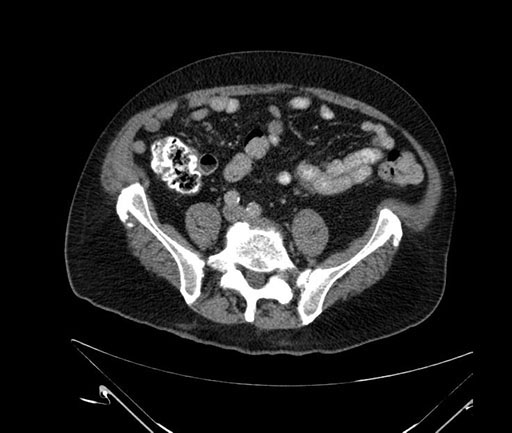

Imaging Analysis

Look through the patient's CT scan to identify any areas of concern for the necessary procedure.

Based on your CT findings, which issue(s) would give reason for "planned slowing down moment(s)" in this case?

Considering a standard Whipple procedure, what step(s) of the operation would you do differently in this case?